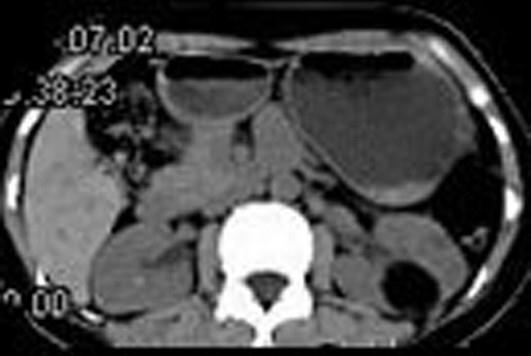

问题 女,38岁,体检时B超在左肾探及一中强回声光团,边界清,内部回声均匀,CT检查如图所示,下列说法正确的是 ( )

选项 A、考虑为左肾血管平滑肌脂肪瘤 B、考虑为左肾脂肪瘤 C、病灶与周围肾组织界限清楚 D、病灶密度为脂肪密度 E、左肾中部靠后方可见一类圆形低密度病灶

答案 BCDE